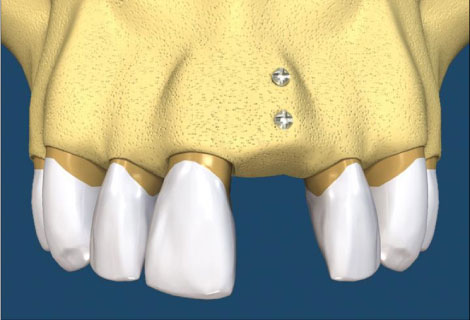

自體骨移植術是患者本身要植牙的位置缺少骨頭,用病患自己身上的骨頭或骨屑,移植到要植牙但缺少骨頭的區域。骨頭的來源不限於口腔內,尤其是缺很多骨頭時,像是口腔癌或是特殊的患者,骨頭的來源可能是肋骨或腿骨,平常較常見的是若骨頭缺損比較多的情況下,從下巴處或智齒後取得骨塊;如缺損比較少時,會利用做植牙手術在鑽骨頭時,收集鑽骨所產生的骨屑來補,簡單來說就是拿病人自己的骨頭來補缺損、不足的地方。病患不用擔心自體骨移植是否會產生排斥的現象,因為自體骨移植是取自於自己身上的骨頭,所以並不會產生排斥的現象,新種下去的骨頭或骨粉經重新生長過後與底下的骨頭結合。自體骨移植相對於植牙而言,不一定會比較便宜或比較貴,因為費用會因病人的狀況、手術施作的難度而有所影響,因為簡單的可能只是稍微的將骨頭刮一刮就可以補了,但也有可能是需要另外從身體別處取得較大量的骨頭,相對而言後者就困難許多,因此手術費用的高低會因為手術的困難程度而有所影響。(圖26-29)

圖26

圖27

圖28

圖29